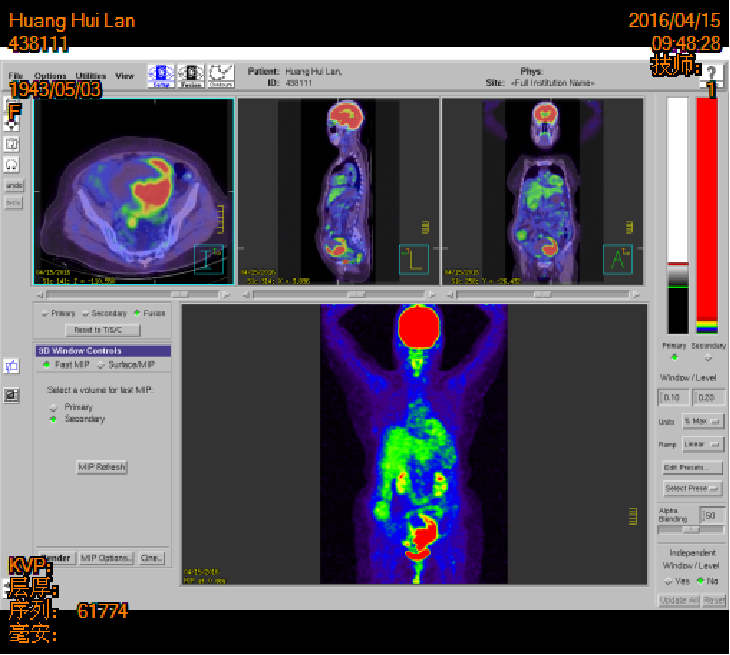

2016-04-15 PET-CT

左侧附件区肿块,代谢活跃,考虑卵巢囊腺癌;直肠壁增厚,代谢活跃,考虑直肠癌并周围淋巴结转移可能性大,建议肠镜检查;双肺多发结节,考虑转移瘤;腹腔积液